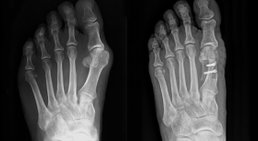

Als Facharzt für Orthopädie und Orthopädische Chirurgie habe ich mich auf die Behandlung von Verletzungen und Erkrankungen des Fußes, des Knies und der Hüfte spezialisiert.

Übermäßige Beanspruchung, Verletzungen sowie angeborene und erworbene Fehlbildungen des Fußes und des Beines können sich negativ auf die Beweglichkeit und Lebensqualität auswirken und zu zahlreichen Folgeerkrankungen und Fehlhaltungen führen. Dank meiner langjährigen Erfahrung bin ich mit unterschiedlichsten Formen von Beeinträchtigungen und Problemen des Vor- und Rückfußes und der unteren Extremität bestens vertraut und kann meinen Patienten eine umfassende Betreuung bieten, die darauf abzielt, dass Sie sich wieder schmerzfrei durch den Alltag bewegen können.

Vorfuß-Beschwerden